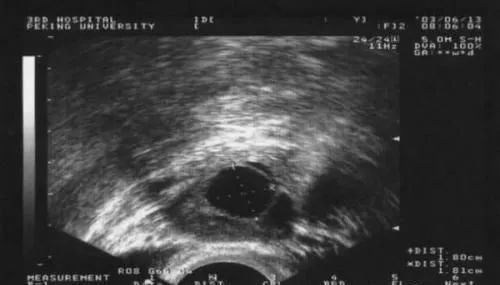

5.B超檢測(cè):一般在月經(jīng)的第10-12天開(kāi)始監(jiān)測(cè),若需要促排卵的患者一般在月經(jīng)第5天開(kāi)始促排卵,第10天復(fù)查B超。當(dāng)卵泡生長(zhǎng)到18-20mm時(shí)卵泡成熟,即將排卵;卵泡消失或體積明顯縮小,邊緣皺縮,出現(xiàn)鋸齒狀,后穹窿出現(xiàn)積液是說(shuō)明卵泡已破裂,排出卵泡液。

總之,最直接的監(jiān)測(cè)方式就是陰道B超檢測(cè)排卵。